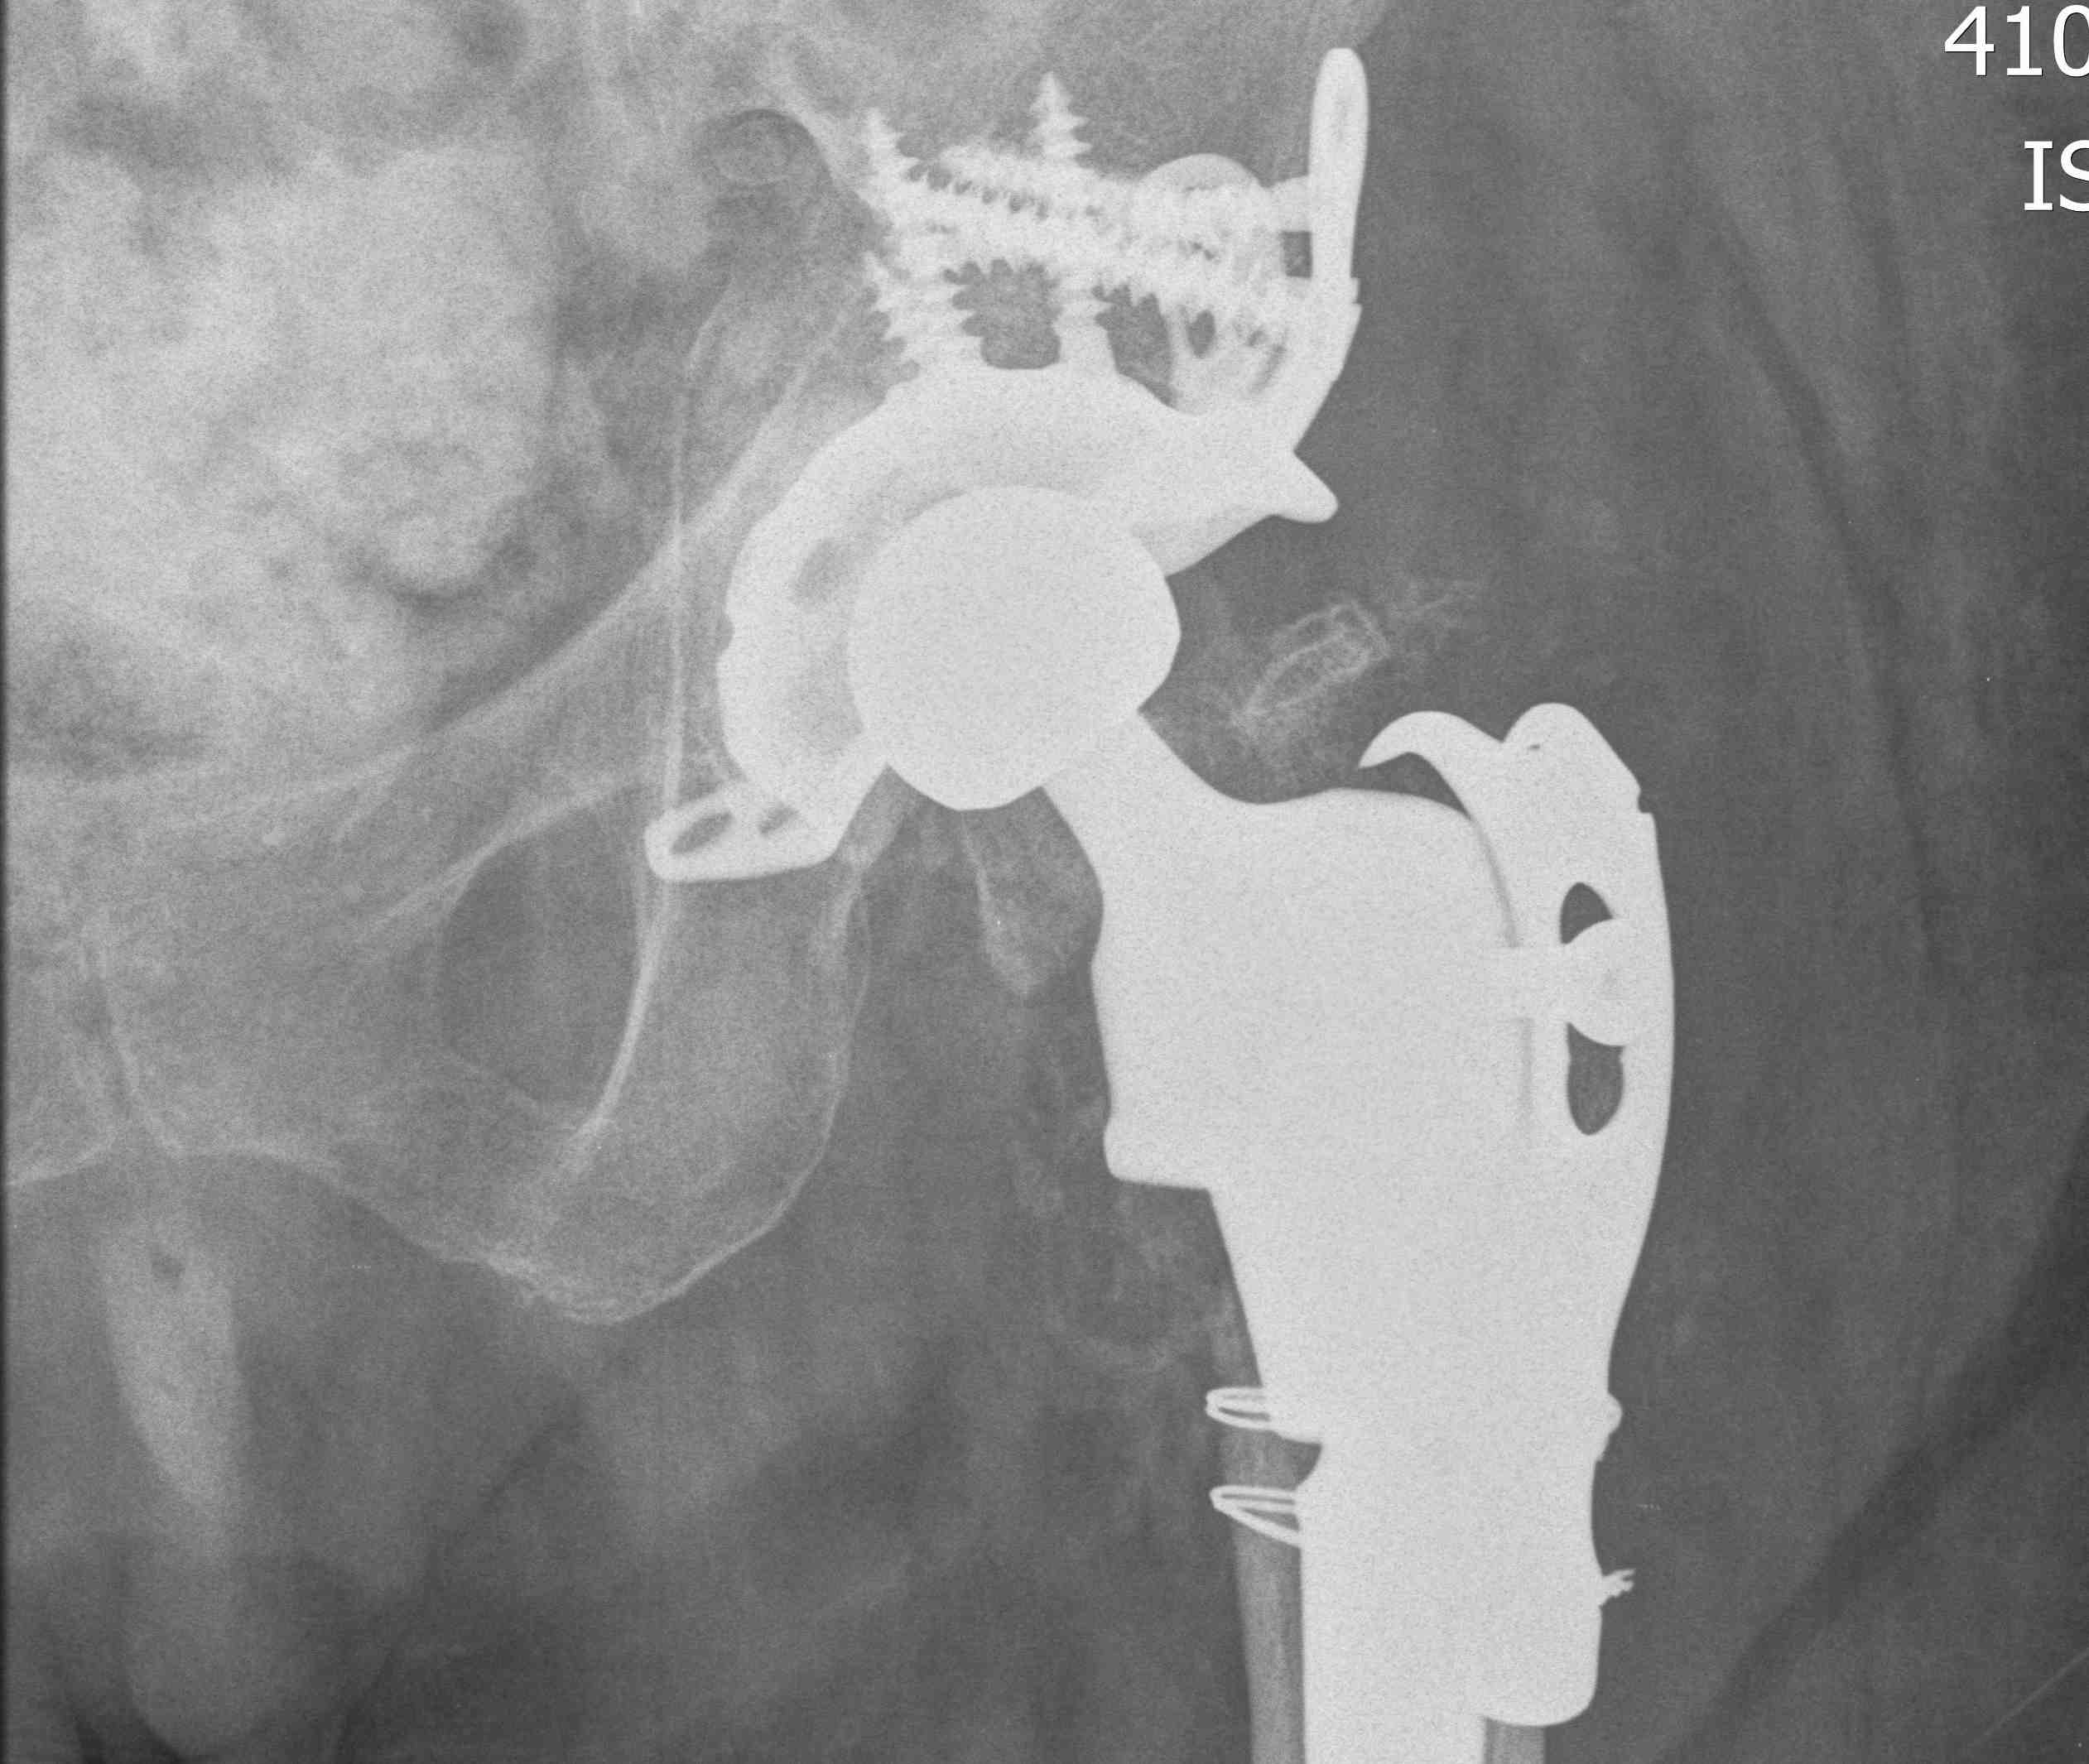

Total hip arthroplasty

Indications

Young, active, mobile patient with neck of femur fracture

Issues

THA

- better functional outcome in young mobile patient

- higher cost

- higher dislocation rates

Australian Joint Registry 2023

- 27,500 primary THA for fracture hip

- revision rate 9% at 15 years

- revision for dislocation 1.5%

- revision for fracture 2%

- revision for infection 1%

- revision for loosening 1.5%